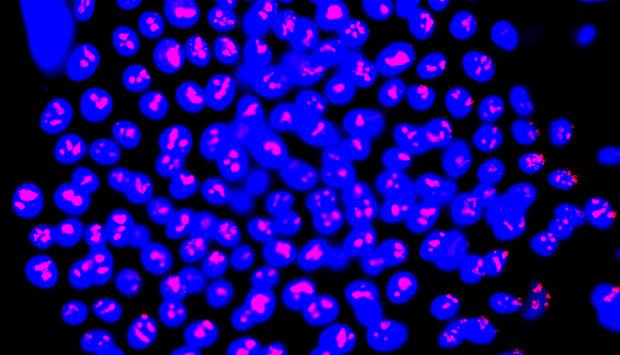

ATP-binding-cassette G2 (ABCG2)-positive skin cells (blue) show positive staining of cell proliferation marker Ki-67 (red), which marks cells with the most growth potential.

© 2016 Dongrui Ma, Singapore General Hospital

“Cultured grafts are usually very fragile,” says Birgit Lane from the A*STAR Institute of Medical Biology. Researchers sought to ‘enrich’ and fortify the grafts by including more stem cells, a cell type with potent tissue repair capability. They needed a cellular marker to identify skin stem cells: a protein usually tasked with evicting foreign chemicals from cells, ATP-binding-cassette G2 (ABCG2), fitted the bill.

Promisingly, “ABCG2 is a cell-surface marker, so we can isolate live cells using a cell-sorting technology,” says Dongrui Ma, the paper’s lead author. Often, stem cell markers cannot target live cells, which limits their clinical applications.